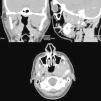

Presentamos a un paciente varón de 32 años, que acudió a las consultas externas del Servicio de Cirugía Oral y Maxilofacial del Hospital POVISA de Vigo por molestias en la articulación temporomandibular izquierda, de meses de evolución. Refería además chasquidos articulares y dolor ocasional no intenso. Su historia clínica no reflejaba ningún antecedente personal de interés. En la exploración física presentaba una asimetría facial, palpándose una tumefacción preauricular izquierda; la exploración intraoral era anodina y no existía limitación de la apertura oral. Se realizó una ortopantomografía, sin mostrar ninguna alteración ósea, por lo que se procedió a realizar una resonancia magnética, tras la administración de gadobutrol intravenoso (fig. 1). Esta mostraba una tumoración con componente sólido y quístico localizada en el espacio masticador izquierdo, con unas medidas de 2,5cm de diámetro transversal, 3,5cm de diámetro anteroposterior y 4,3cm de diámetro craneocaudal, con bordes bien definidos. Tras la administración de contraste, la tumoración presentaba una captación muy escasa e irregular. No se podía descartar ni confirmar la presencia de calcificaciones. La morfología del cóndilo se encontraba respetada, pero se podía evidenciar una destrucción secundaria de la fosa glenoidea, con extensión a la base del cráneo, desplazando el lóbulo temporal. La primera posibilidad diagnóstica a considerar con estos hallazgos fue un sarcoma sinovial, siendo otras posibilidades a valorar una condromatosis sinovial (aunque no parecían evidenciarse calcificaciones) o un granuloma reparativo de células gigantes. Se realizó TC facial (fig. 2) para poder valorar mejor las estructuras óseas y la existencia de calcificaciones; esta mostró una masa sólida redondeada localizada entre el ala externa de la apófisis pterigoides izquierda y el cóndilo del mismo lado, con unas medidas de 3,6×2,9×3,4cm. Tras la administración de contraste intravenoso presentaba un realce heterogéneo. La masa erosionaba la fosa temporal de la articulación, y presentaba un crecimiento intracraneal, ocupando la porción más lateral de la fosa craneal media, con unas medidas de 2,4cm de diámetro transversal y 1,4cm de diámetro craneocaudal. Producía además reacción perióstica, afectando fundamentalmente a la parte más anterior del cuello condilar y a la cara lateral de la rama mandibular. Por tanto, se trataba de una lesión con características radiológicas de agresividad. La primera posibilidad diagnóstica en el diagnóstico diferencial fue la de sarcoma sinovial, sin poder descartar rabdomiosarcoma; otras lesiones agresivas de la articulación parecían menos probables, por las características de captación de contraste, entre ellas la sinovitis villonodular pigmentaria o la condromatosis sinovial (en nuestro caso no se evidenciaban cuerpos libres calcificados).

En las imágenes de la TC preoperatoria podemos identificar una masa sólida redondeada localizada entre el ala externa de la apófisis pterigoides izquierda y el cóndilo ipsolateral; en los cortes coronales y sagitales podemos ver la extensión intracraneal de la lesión, ocupando la parte más lateral de la fosa craneal media.